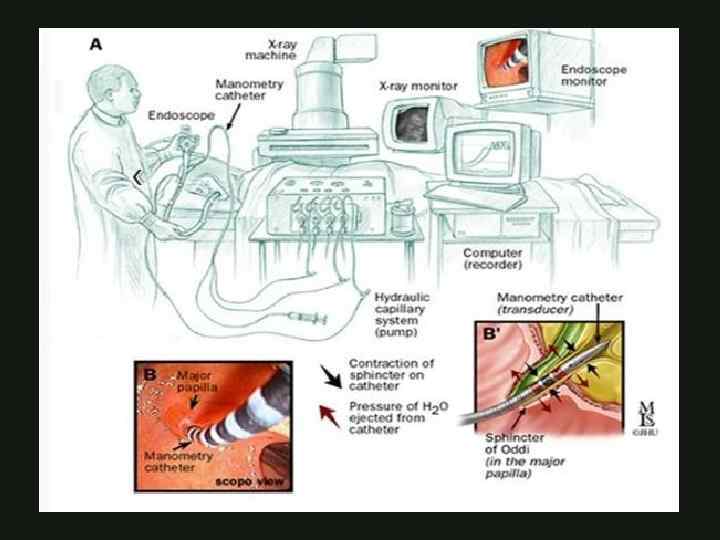

ЭНДОСКОПИЧЕСКОЕ ЛЕЧЕНИЕ ОСТРОГО ОТЕЧНОГО ПАНКРЕАТИТА Эндоскопическая папилосфинктеротомия Эндоскопическое стентирование ЭРХПГ КАФЕДРА ХИРУРГИИ МОСКОВСКОГО ФАКУЛЬТЕТА

ЭНДОСКОПИЧЕСКОЕ ЛЕЧЕНИЕ ОСТРОГО ОТЕЧНОГО ПАНКРЕАТИТА Эндоскопическая папилосфинктеротомия Эндоскопическое стентирование ЭРХПГ КАФЕДРА ХИРУРГИИ МОСКОВСКОГО ФАКУЛЬТЕТА